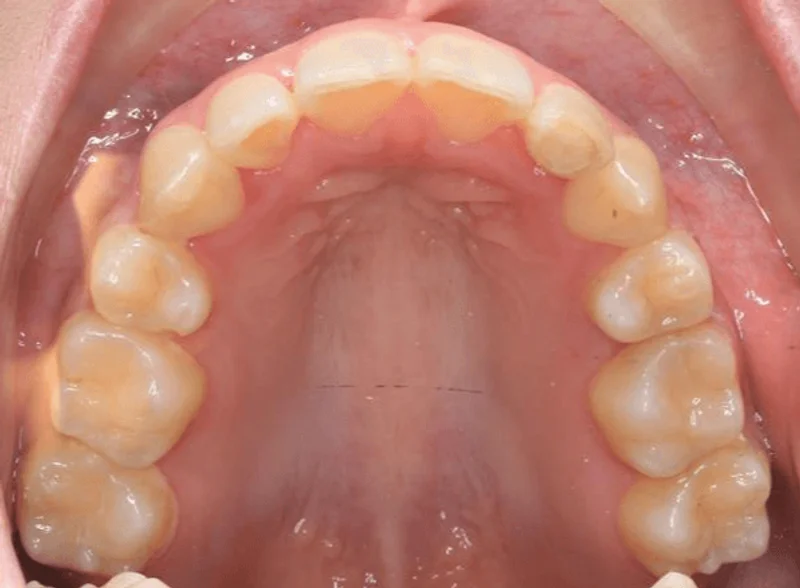

Upper Occlusal

Upper Occlusal - Before Treatment

Before